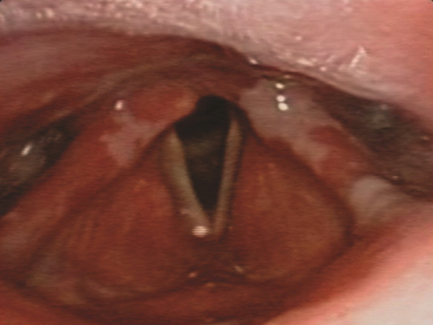

Se decidió aumentar la prednisona a 50 mg/día vía oral y se completaron siete días con cefotaxima. Se realizó endoscopia nasofaríngea, demostrándose mucositis amplia de cavidad oral, con extensión a faringe y laringe, sin compromiso de mucosa nasal (figura 2). Además, se tomó biopsia de la mucosa del labio inferior y glándula salival, en la que se registró mucosa ulcerada sin epitelio valorable, con sialoadenitis crónica.

Figura 2 Placas blanquecinas en mucosa de hipofaringe, con edema circundante a nivel de ambos senos piriformes y valleculas.